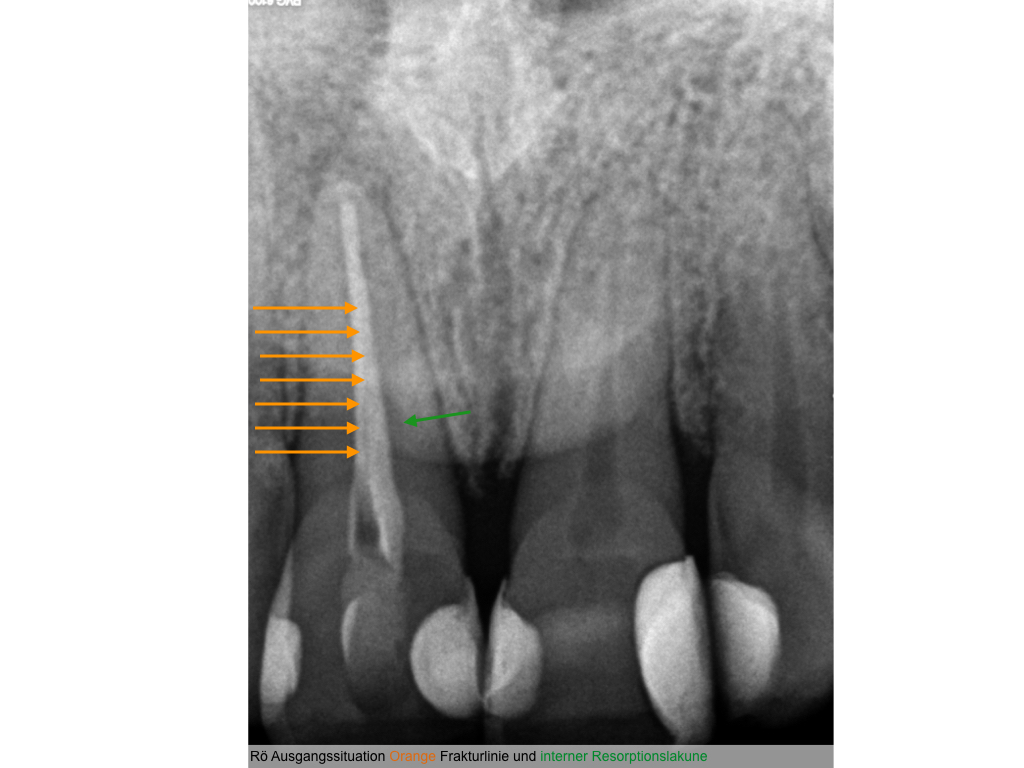

Vorsicht Falle (1) – Infraktur